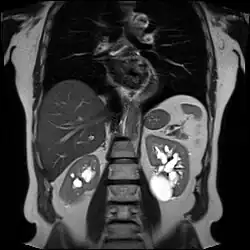

![]() | |

| Renal cyst of the left kidney (hyperintense area) as shown on MRI. | |